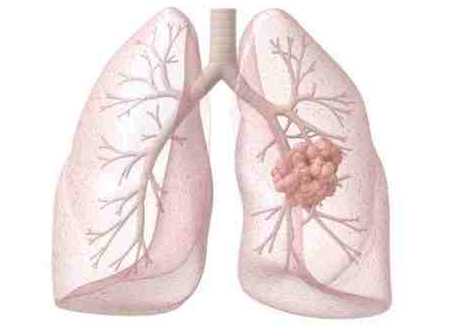

对于 EGFR 突变和 ALK 重排非小细胞肺癌(NSCLC),脑转移(BM)是诊断和复发时的第二常见部位。25%~50% NSCLC 在整个疾病过程中出现 BM。30%~60% EGFR 突变、40%~70% ALK+ 患者发生 BM。

BM 影响生存期和生活质量,预期生存期(OS)3~15 个月。因药物很难透过血脑屏障(BBB),放疗是脑转移的治疗基石。对不适合手术或 SRS 的患者,一直以来全脑放疗(WBRT)作为首选。近年来靶向药物如酪氨酸激酶抑制剂(TKIs)对颅内病灶疗效显着,脑脊液(CSF)药物浓度增加。

单发或寡转移考虑局部治疗如 SRS,对 10 个以下脑转移 SRS 是安全的。不适合局部治疗的,保护海马区 WBRT 可减轻神经毒性。靶向治疗透过血脑屏障能力增强,显着改善 NSCLC 脑转移预后。对于驱动基因阳性患者,放疗联合靶向治疗策略可以用于处理颅内转移患者。免疫治疗对于肺癌脑转移有效,脑放疗联合免疫治疗的研究较少。